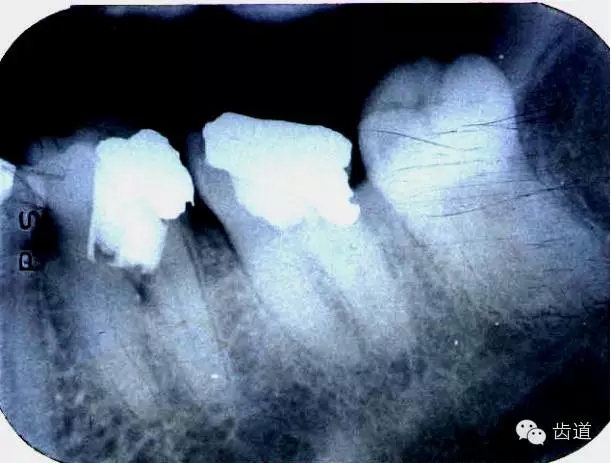

左上7近中頰根器械折斷

右上6腭根器械折斷

折斷于根管內(nèi)的器械要盡量取出,若無(wú)法取出經(jīng)常規(guī)充填后,成功率不受明顯影響。

1.折斷器械有一部分露在根管口外,用鑷子或持針器夾取出。

2.器械斷端在根管口內(nèi):用超聲根管銼在該器械旁增隙,通過(guò)超聲震蕩和沖洗,可將折斷器械從根管內(nèi)震動(dòng)沖出。在手術(shù)顯微鏡下直視操作,大大提高了取出的成功率。

3.折斷器械尖端已超出根尖孔:無(wú)癥狀不處理;有疼痛則作根尖手術(shù)取出。

4.折斷器械較長(zhǎng),各種方法均不能取出,可作根管電解消毒,塑化治療或塑化劑處理,根管充填。

若患牙根尖有病變,必要時(shí)作根尖切除+倒充填。